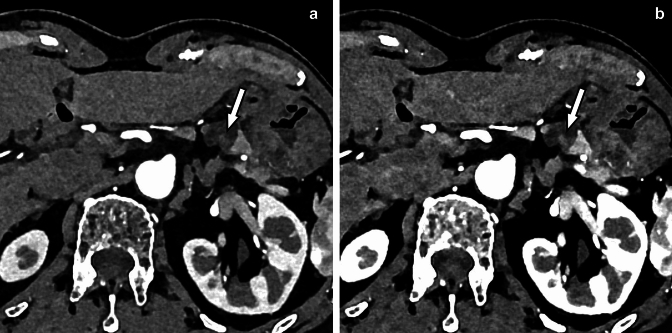

Fig. 11.

A small thrombus in the mesenteric vein (arrows) is visualized on the photon-counting CT images at 70 (A) and 50 keV (B). The 50 keV image (B) shows the thrombus with higher contrast than the 70 keV image (A). Photon-counting CT is excellent for visualization of venous thrombus